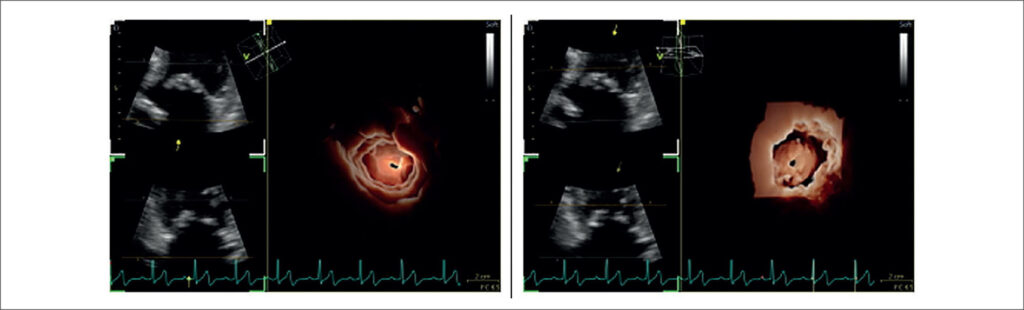

My Approach to Three-Dimensional Echocardiography in Mitral Stenosis: How and When?

Three-dimensional echocardiography has become an essential tool in the assessment of mitral stenosis, allowing detailed anatomical analyses and reliable measurements, even in complex anatomies or extensive calcification. Based on daily clinical experience in an imaging laboratory, this article offers a practical guide for image acquisition and optimization, multiplanar reconstruction, and three-dimensional planimetry, focusing on technical adjustments, the use of tools such as rotation and cropping, and strategies for integrating the method into the routine workflow of cardiovascular imaging centers.